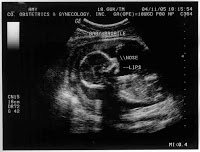

I had attached an image that I scanned in at work: our ultrasound picture from five weeks before then that showed our Doodlebug at 12 weeks of age in utero.

She’s just a little bean in there. We didn’t even know she was a she at that point.